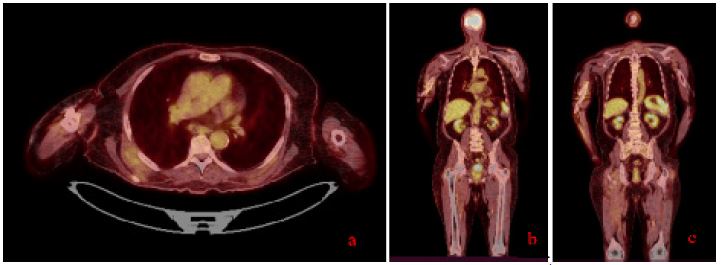

The patient demonstrated a significant clinical improvement following 3 weeks of the initiation of daratumumab and lenalidomide therapy. Serial imaging studies, done in january 2025, showed a marked reduction in the size of both the humeral and pancreatic masses, with complete resolution of the lytic bone lesion and near-total disappearance of the pancreatic mass. These findings were corroborated by clinical evaluation, with the patient reporting resolution of symptoms such as pain and swelling at the site of the previous humeral mass.

Figure 3: (A-C) Different sections of the patient’s follow up PET CT scan (January 2025) showing a complete morpho-metabolic remission of the large intensely hypermetabolic tissue mass in the pancreatic head and complete metabolic remission of the large intensely hypermetabolic skeletal muscle tissue mass in the right arm with humeral involvement, described on the PET scan of September 30, 2024.

As of the latest follow-up, the patient continues to show complete morpho-metabolic remission, with no new hypermetabolic lesions identified on PET-CT since January 2025.